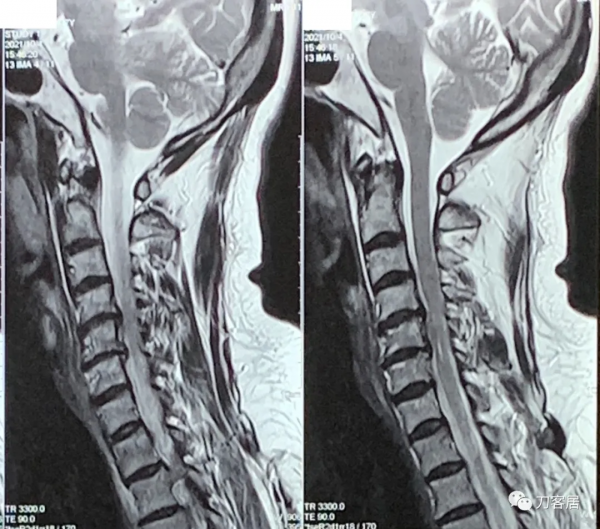

自帶腰椎MRI未見嚴重的椎間盤突出及椎管狹窄。自帶髖關節MRI未見異常,自帶胸椎MRI未見異常。自帶頸椎MRI提示頸4-5,頸5-6椎間盤突出,頸椎失穩。

圖9. 20211004頸椎MRI矢狀面T2相及橫截面。提示頸4-5,頸5-6,頸6-7椎間盤突出,椎管狹窄,脊髓訊號改變。

圖10. 20211004頸椎MRI矢狀面T2相及橫截面。提示頸4-5,頸5-6,頸6-7椎間盤突出,椎管狹窄,脊髓訊號改變。

圖11. 20211004頸椎MRI矢狀面T2相,提示頸4-5,頸5-6,頸6-7椎間盤突出,椎管狹窄,脊髓訊號改變。

圖12. 20211004頸椎MRI矢狀面T2相,提示頸4-5,頸5-6椎間盤突出,椎管狹窄,脊髓訊號改變。此兩間隙應該是責任間隙。也應存在頸4-5,頸5-6之間的不穩。

圖13. 20211004頸椎MRI矢狀面T1相,提示頸4-5,頸5-6椎間盤突出,椎管狹窄,脊髓訊號改變。此兩間隙應該是責任間隙。也應存在頸4-5,頸5-6之間的不穩。

圖14. 20211004頸椎MRI矢狀面T1相,提示頸4-5,頸5-6椎間盤突出,椎管狹窄,脊髓訊號改變。此兩間隙應該是責任間隙。也應存在頸4-5,頸5-6之間的不穩。

圖15. 20211004頸椎MRI矢狀面T2相及橫截面。提示頸4-5,頸5-6,頸6-7椎間盤突出,椎管狹窄,脊髓訊號改變。